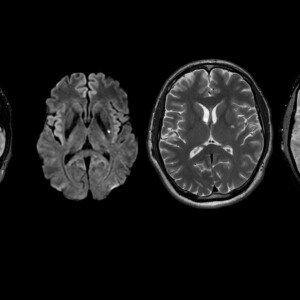

Στα διαγνωστικά κέντρα Ιατροδιάγνωση χρησιμοποιούνται υπερσύγχρονoi μαγνητικοί τομογράφοι υψηλού μαγνητικού πεδίου (1,5T) του Αμερικανικού οίκου GE, εξασφαλίζοντας υψηλή ευκρίνεια και ακρίβεια εικόνας.

O μαγνητικός τομογράφος με τον μεγάλο αριθμό καναλιών που διαθέτει, την μεγάλη διάμετρο (wide bore),το μικρό μήκος μηχανήματος, τα σύγχρονα συστήματά και το εξειδικευμένο προσωπικό επιτυγχάνεται ο μειωμένος χρόνος εξέτασης, η άνεση και η υψηλή ακρίβεια.

Σε αυτή την εξέταση απεικονίζεται με τη χρήση ή χωρίς σκιαγραφικού μέσου το παρέγχυμα ,τα οστά και όλες οι δομές του εγκεφάλου των νεύρων και του νωτιαίου μυελού διαγιγνώσκοντας παθήσεις όπως υδροκεφαλία, ριζίτιδες, όγκους κ.α.

Απεικονίζεται η νευρωνική δραστηριότητα του εγκεφάλου μέσω των αιμοδυναμικών αντιδράσεων αυτού. Με αυτό τον τρόπο καθώς και με την δεμιτογραφία (DIT) ελέγχονται κέντρα που ελέγχουν την ομιλία, την μνήμη και την κίνηση γι’αυτό πολλές φορές ο ασθενής συμμετέχει στην εξέταση ακολουθώντας οδηγίες (π.χ. ανασ;hκωση χεριού κ.α.)

Eλέγχεται η μεταβολική δραστηριότητα του εγκεφάλου. Αποτελεί σημαντικό εργαλείο για όγκους, απομυελυνωτικές εστίες κ.α.)